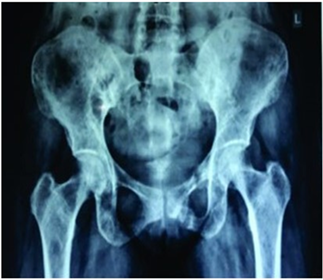

A case of 36-year-old female who was referred from orthopedics department of clinical hematology with complaint of back pain, anemia (8.2 gm/dl), hypercalcemia (11.1 mg/dl) and multiple lytic lesions in pelvic and sacral bone on X-ray (Figure 1). Renal function test and liver function test were normal except markedly elevated serum alkaline phosphatase (593 U/L). Bone marrow was done to rule out multiple myeloma.

Figure 1: Digital X ray showing multiple lytic lesions in Ileum, pubic rami and right femur bone.